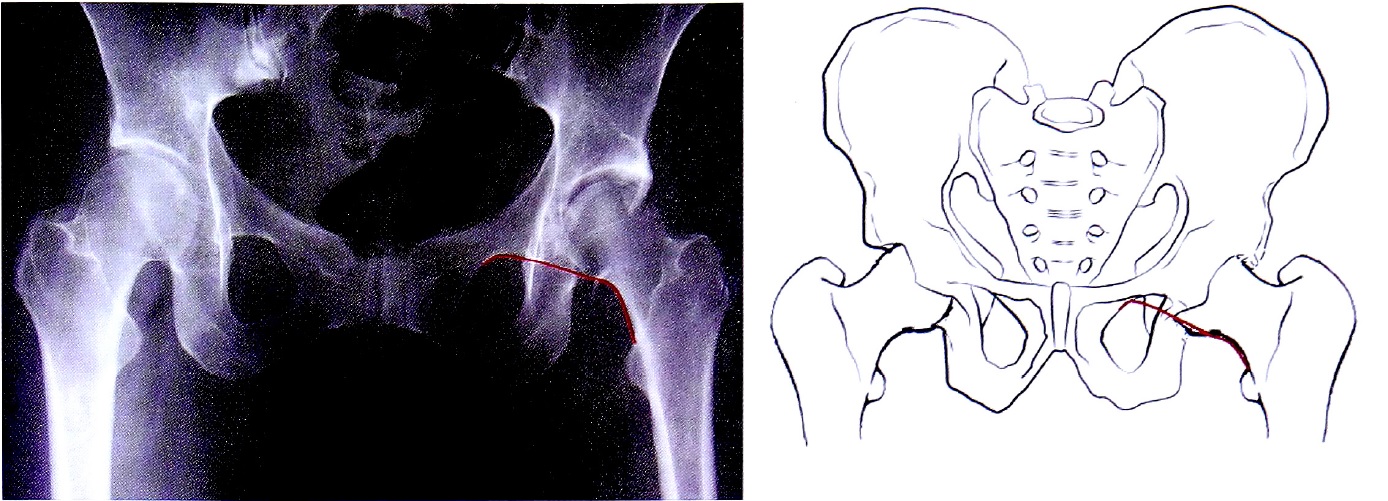

С помощью рентгенограммы в косой запирательной проекции, выполненной по методике НМИЦ ТО, диагностирован перелом задней стенки со смещением отдельного фрагмента. Также с помощью прицельного снимка определена целостность контуров запирательного отверстия (рис. 15).

Рис. 15. Рентгенография правого тазобедренного сустава в косой-запирательной проекции, выполнена по методике НМИЦ ТО. Стрелками показан перелом и отдельный фрагмент задней стенки.

Fig. 15. Obturator oblique view made with CITO method. Arrows shows separated posterior wall fragment.

Рентгенограмма в косой запирательной проекции (наличие смещенного фрагмента задней стенки) подтверждает установленный диагноз (рис. 21). Достоверность диагноза подтверждается наличием рентгенологических признаков перелома на рентгенограммах как минимум в 2-х проекциях во взаимно перпендикулярных или близких к этому плоскостях.

Рис. 21. Верификация перелома задней стенки по данным косой запирательной проекции.

Fig. 21. Posterior wall fracture verification on obturetor oblique view.